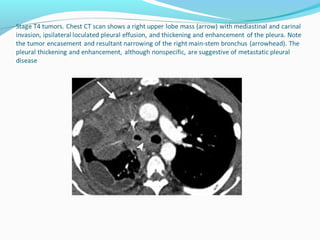

T4 - tumor

Invasion of vital mediastinal structures: fat, heart, trachea,

esophagus, great vessels, recurrent laryngeal nerve, carina.

Invasion of vertebral body.

Malignant pleural or pericardial effusion (cytologically

proven).

Separate tumour nodule(s) in a different ipsilateral lobe to

that of the primary tumor.

T4 - tumor Invasionof vital mediastinal structures: fat, heart, trachea, esophagus, great vessels, recurrent laryngeal nerve, carina. Invasion of vertebral body. Malignant pleural or pericardial effusion (cytologically proven). Separate tumour nodule(s) in a different ipsilateral lobe to that of the primary tumor.